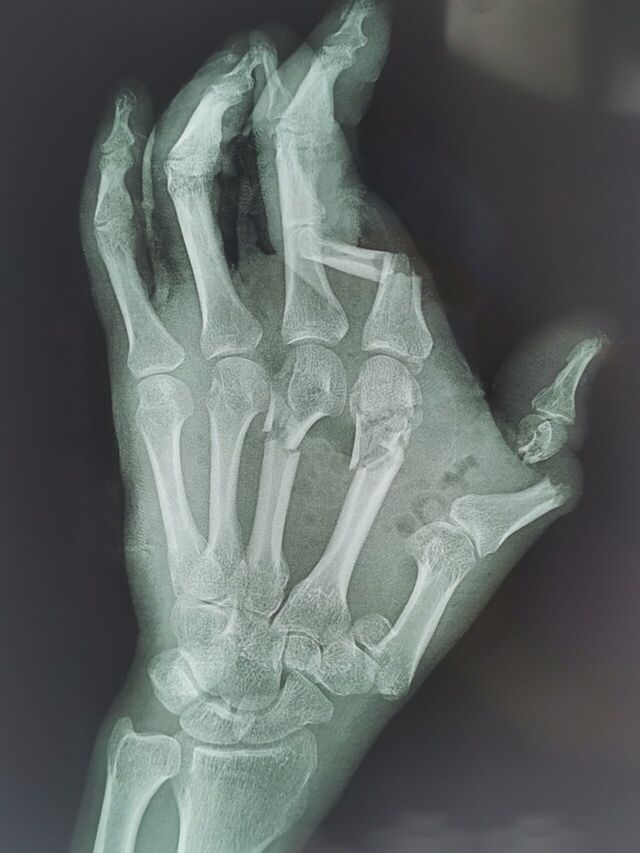

拇指先天畸形

mmexport1754487711297.jpg

mmexport1754487742008.jpg